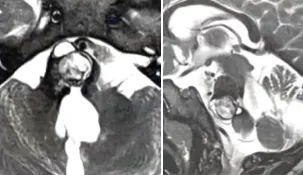

最终家属选择请德国巴特朗菲教授主刀。手术当日,娜娜看到许多不同年龄的患儿同样等待手术。当她苏醒时,听到母亲激动的声音:"娜娜的肿瘤终于切干净了!"

本案例选自巴特朗菲教授年会演讲案例集。需要特别说明的是,脑干出血患者确实面临较高风险,早期手术是最佳治疗选择。虽然患者对再次手术存在恐惧心理,但为挽救生命和支持她的家人,最终克服心理障碍接受手术。选择德国巴特朗菲教授主刀决策正确,术后影像学证实肿瘤全切,患者神经功能恢复顺利,不适症状逐步缓解,取得了令人满意的治疗效果。